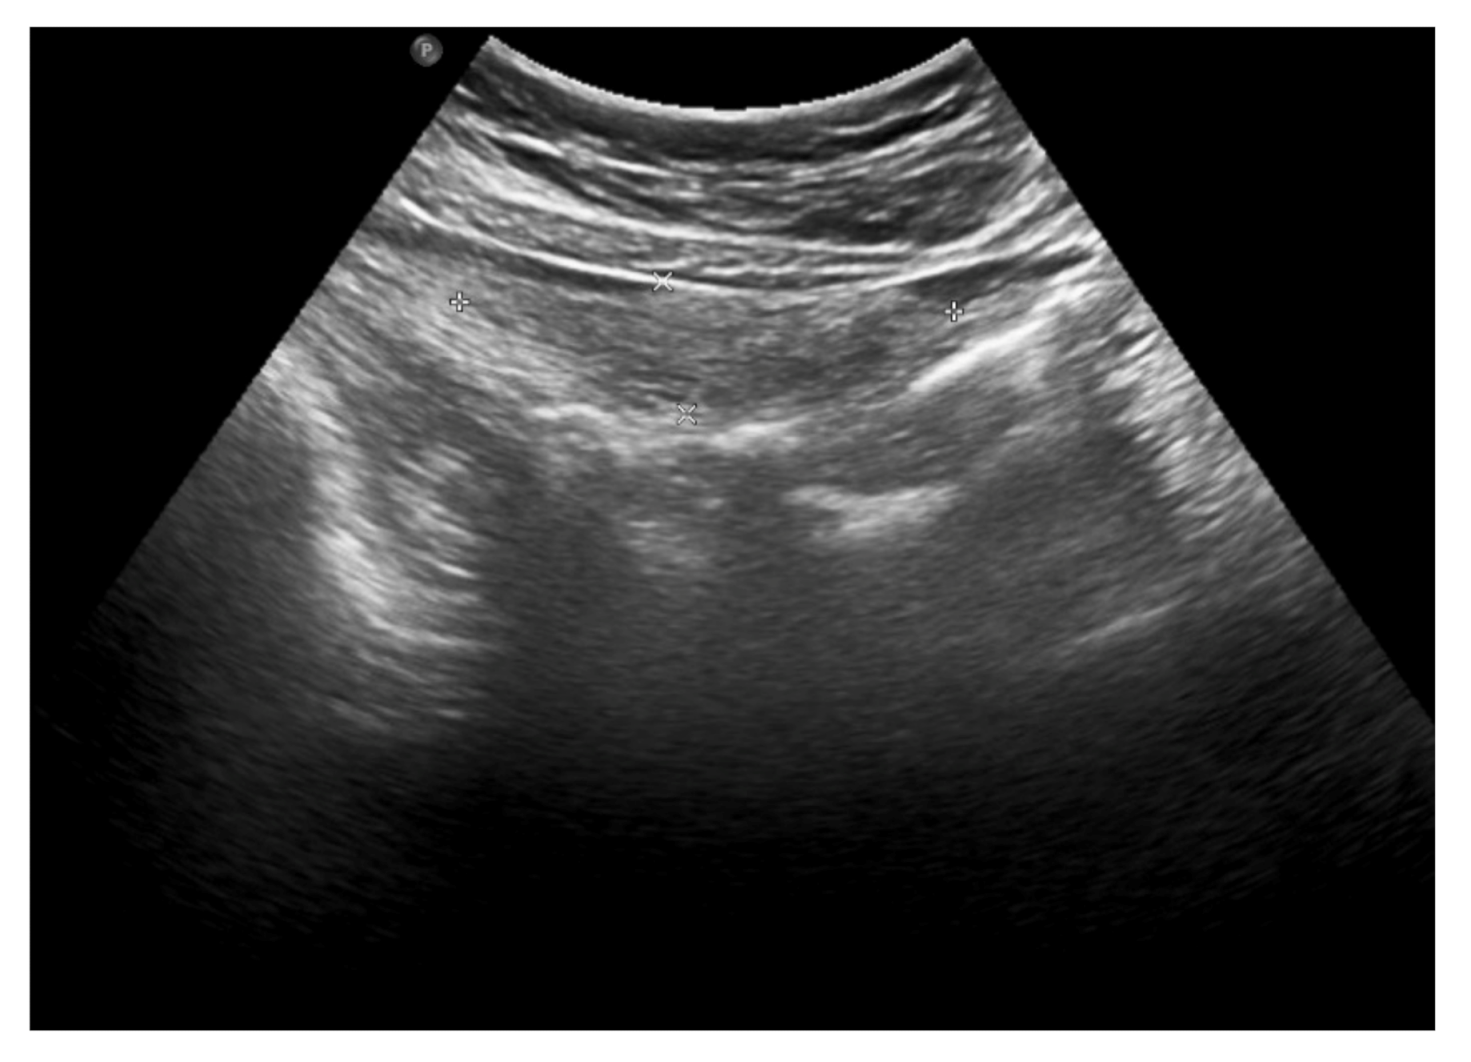

The clinical picture, along with laboratory and imaging investigations, led to the diagnosis of omental infarction. Conservative treatment was introduced. Enema was performed with a good effect. Antibiotic therapy (cefuroxime), analgesic treatment and fluid therapy were implemented. During hospitalization, the subsidence of clinical symptoms and a decline of the inflammatory parameters were observed. In the control abdominal ultrasound, performed on the seventh day of hospitalization, a partial regression of lesions was noted (Figure 4).

Figure 4. The abdominal ultrasound on the seventh day of treatment: partial regression of fluid collections and hyperechoic adipose tissue lesions.